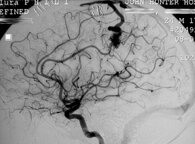

Una cefalea acuta e transitoria può occorrere durante manovre sulle arterie intracraniche, come ad es durante l'esecuzione di una angiografia o un' angioplatica.